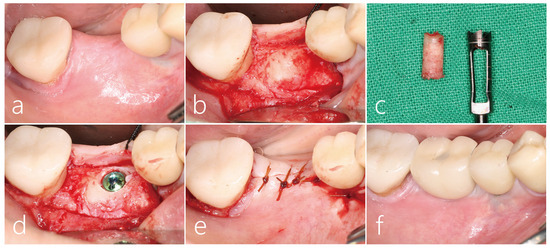

2.1. Case 1

2.2. Case 2

2.3. Case 3

2.4. Case 4